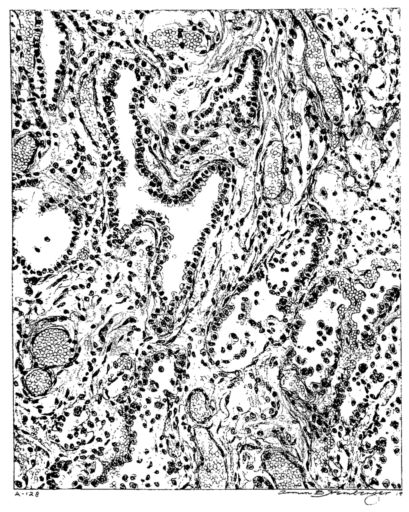

FIG. VII. AUTOPSY NO. 94. A NECROTIZING PROCESS LIKE THAT OF THE TRACHEA ILLUSTRATED IN FIGURE II. HERE IT IS SHOWN TO INVOLVE THE WALL OF THE BRONCHIOLE.

FIG. VIII. AUTOPSY NO. 97. ALTHOUGH THE EPITHELIUM IS STILL VISIBLE AS A HYALINE BAND LIFTED FROM THE UNDERLYING MUCOSA, BOTH MUCOSA AND SUBMUCOSA ARE INVOLVED IN A NECROTIZING PROCESS. BACTERIA ARE ABUNDANT IN THE DEAD TISSUE.

15There is considerable evidence to support the view that the disease spreads from bronchus to bronchus, and in keeping with this view, various stages in the inflammatory processes are more readily determined in these smaller structures than in the trachea. Furthermore, it must be emphasized that even the mildest and the most extreme of these stages are not infrequently encountered in the same lung. The earliest lesion is manifested by an increased homogeneity of the protoplasm of the epithelial lining of the bronchus. The cell protoplasm loses its normal granulation and the nucleus, somewhat darker than usual, becomes conspicuous on a red base (Fig. V). In the lumen of such a tube a serous exudate, perhaps mixed with mucus, is encountered, and there is some spreading apart of the surrounding muscular tissue with engorgement of the vessels. This picture merges gradually into one where the epithelium appears as a homogeneous, red-staining ribbon, devoid of nuclei, often exfoliated, in part at least, from the underlying submucosa (92). The change is traceable through the larger bronchi, even to the ducti alveolares, and not infrequently, bacteria, either as a diffuse, minute dotting or in the form of circumscribed, colony-like formations, are spread through the red, ribbon-like strand (Fig. XVI). With the exfoliation of the epithelial lining, the submucous vessels become more and more conspicuous and may bulge into the lumen of the tube (Fig. VI). That they actually weep into the lumen is proved by the presence of red blood cells in the exudate, now rich in mucus, broken-down nuclei, and desquamated cells. The necrotizing process may not extend deeper than the epithelial lining as is the status described above (140, 162), but it also frequently involves the underlying submucous and muscular layers, so that these lose their identity and stand out as homogeneous masses, in which fragmented nuclei and bacterial accumulations are prominent. Such deeper necrotizing areas may be focal (Fig. VII), or may involve the entire circumference of the tube (Fig. VIII). Occasionally, the epithelium, now dead and staining homogeneously, is lifted from the underlying submucosa in the form of a blister (66), and has very much the same appearance as the well known, early reaction which follows the application of croton oil to the rabbit’s ear. Where this occurs, the submucosa is less involved, as though the necrotizing agent had not penetrated to the same depth and the serous reaction beneath were actually a beneficent exudate. These blisters are in contrast with the deeper areas where the fibrinous mass, mixed with the dead tissue, forms an intensely staining ring or band, which extends through the bronchiolar wall even to the surrounding alveoli.

In the early stage of this process one of the most outstanding features is the absence of polynuclear leucocytes in the reactionary process, but gradually as the dead tissue sloughs away, these cells wander into the exudate and form a purulent ring, more intense in the lumen, but extending for a variable distance through the still viable wall of the structure (47) (Fig. IX). Later mononuclear cells accumulate in this wall and occur either as a diffuse mottling or as circumscribed foci in the muscle and submucous layer of the bronchiole, just as they do in the trachea. Occasionally, a striking change is found in a small bronchiole within a portion of the lung which is otherwise uninvolved by an inflammatory process. Perhaps the alveoli were the seat of a change which has subsided, but, whatever the history, the purulent mass in the bronchiole and involving its wall, stands out effectively (Fig. X).